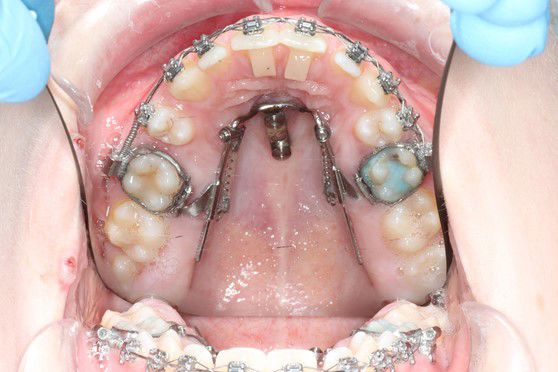

Bruges til at udvide tandbuen i overkæben, f.eks. ved krydsbid.

Den er fastgjort til 6-års tænderne med 2 bånd.

Bruges til at udvide ganen.

Den limes fast på tænderne. Der skal skrues i midten af bøjlen, I får en grundig instruktion på tandreguleringsklinikken.

Der kan opstå lidt spænding ved tænderne, næsen og evt. mellem øjnene.

Ofte kommer der et mellemrum ved fortænderne i en periode.

De indsættes i knoglen under lokalbedøvelse.

De kan sidde enten i den ene side eller i ganen.

Ved hjælp af skruerne kan man flytte enten en eller flere tænder uden at resten af tænderne belastes.

Behandlingen foregår ved, at der indsættes 2 små skruer i ganen under lokalbedøvelse. Derefter fremstilles en ”ganebøjle”, der skues fast på ganeskruerne og sættes ind i bånd, der er limet fast på 6-års tænderne. To små fjedre skubber tænderne frem.